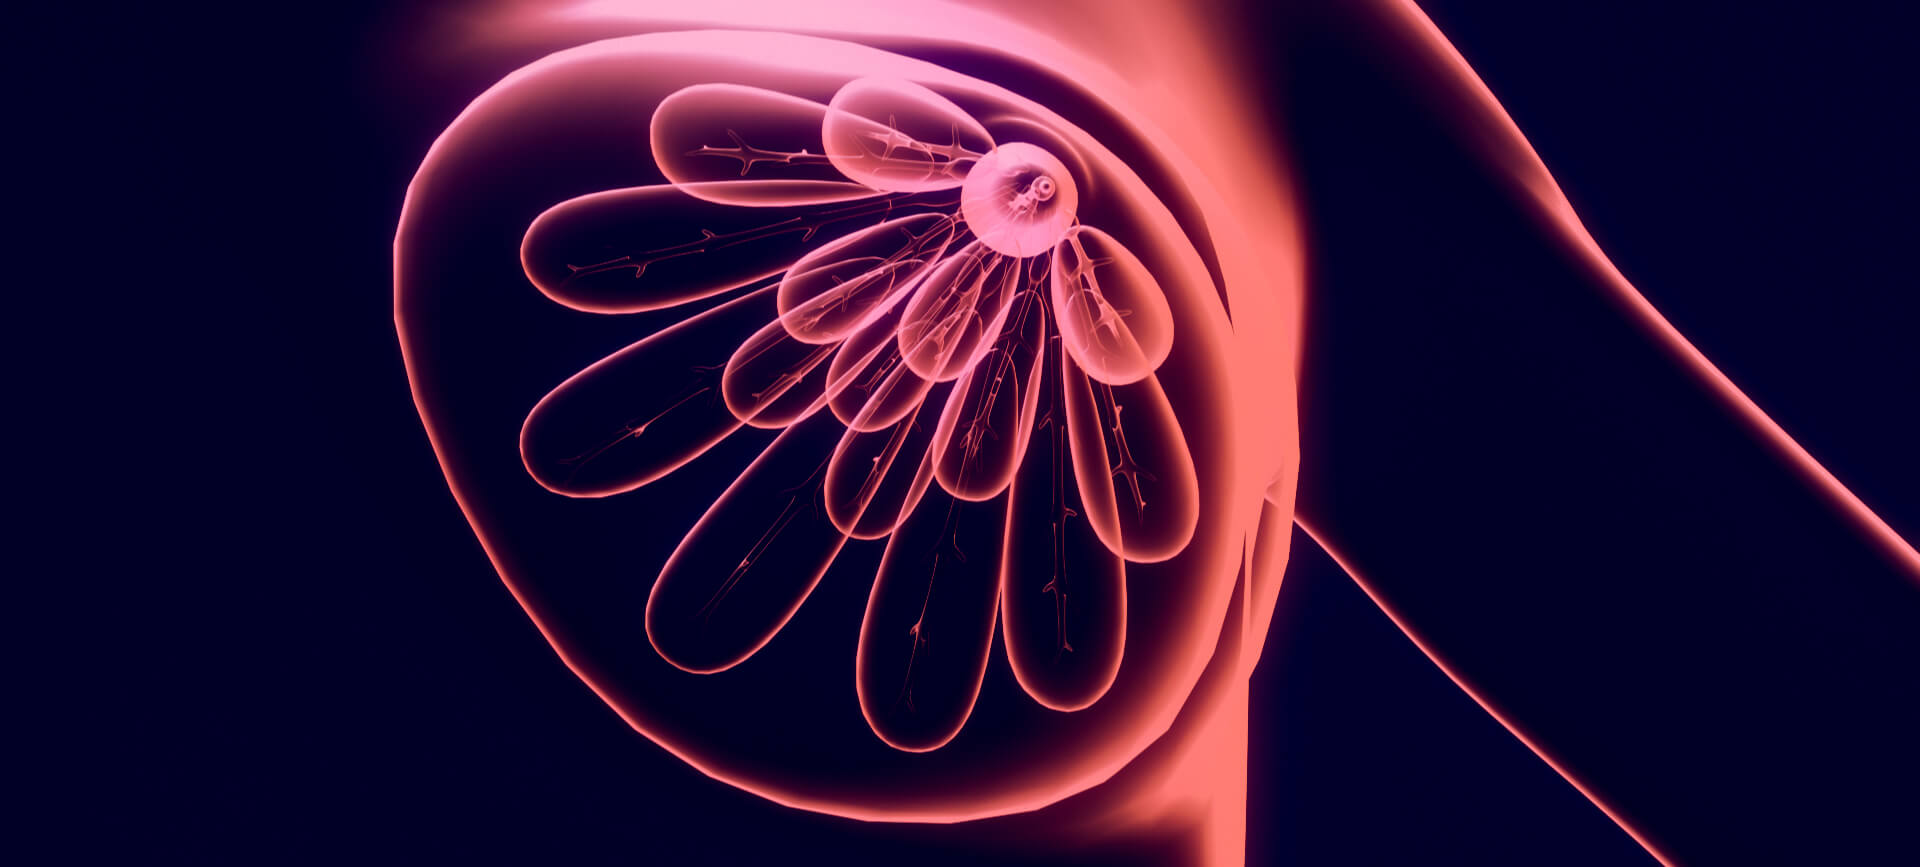

Mammograms

Breast density may not affect a woman’s day-to-day life, but it can correlate to breast cancer.

Can Fibroadenomas Turn Into Breast Cancer?

Found in women’s breast tissue, complex fibroadenomas may increase the risk of breast cancer.